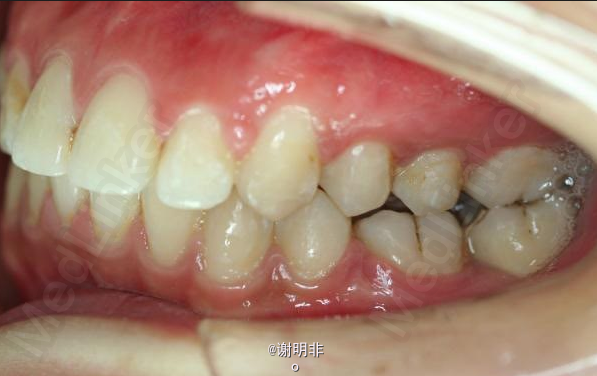

又一例不对称拔牙

牙弓狭窄,牙列拥挤

不对称拔牙